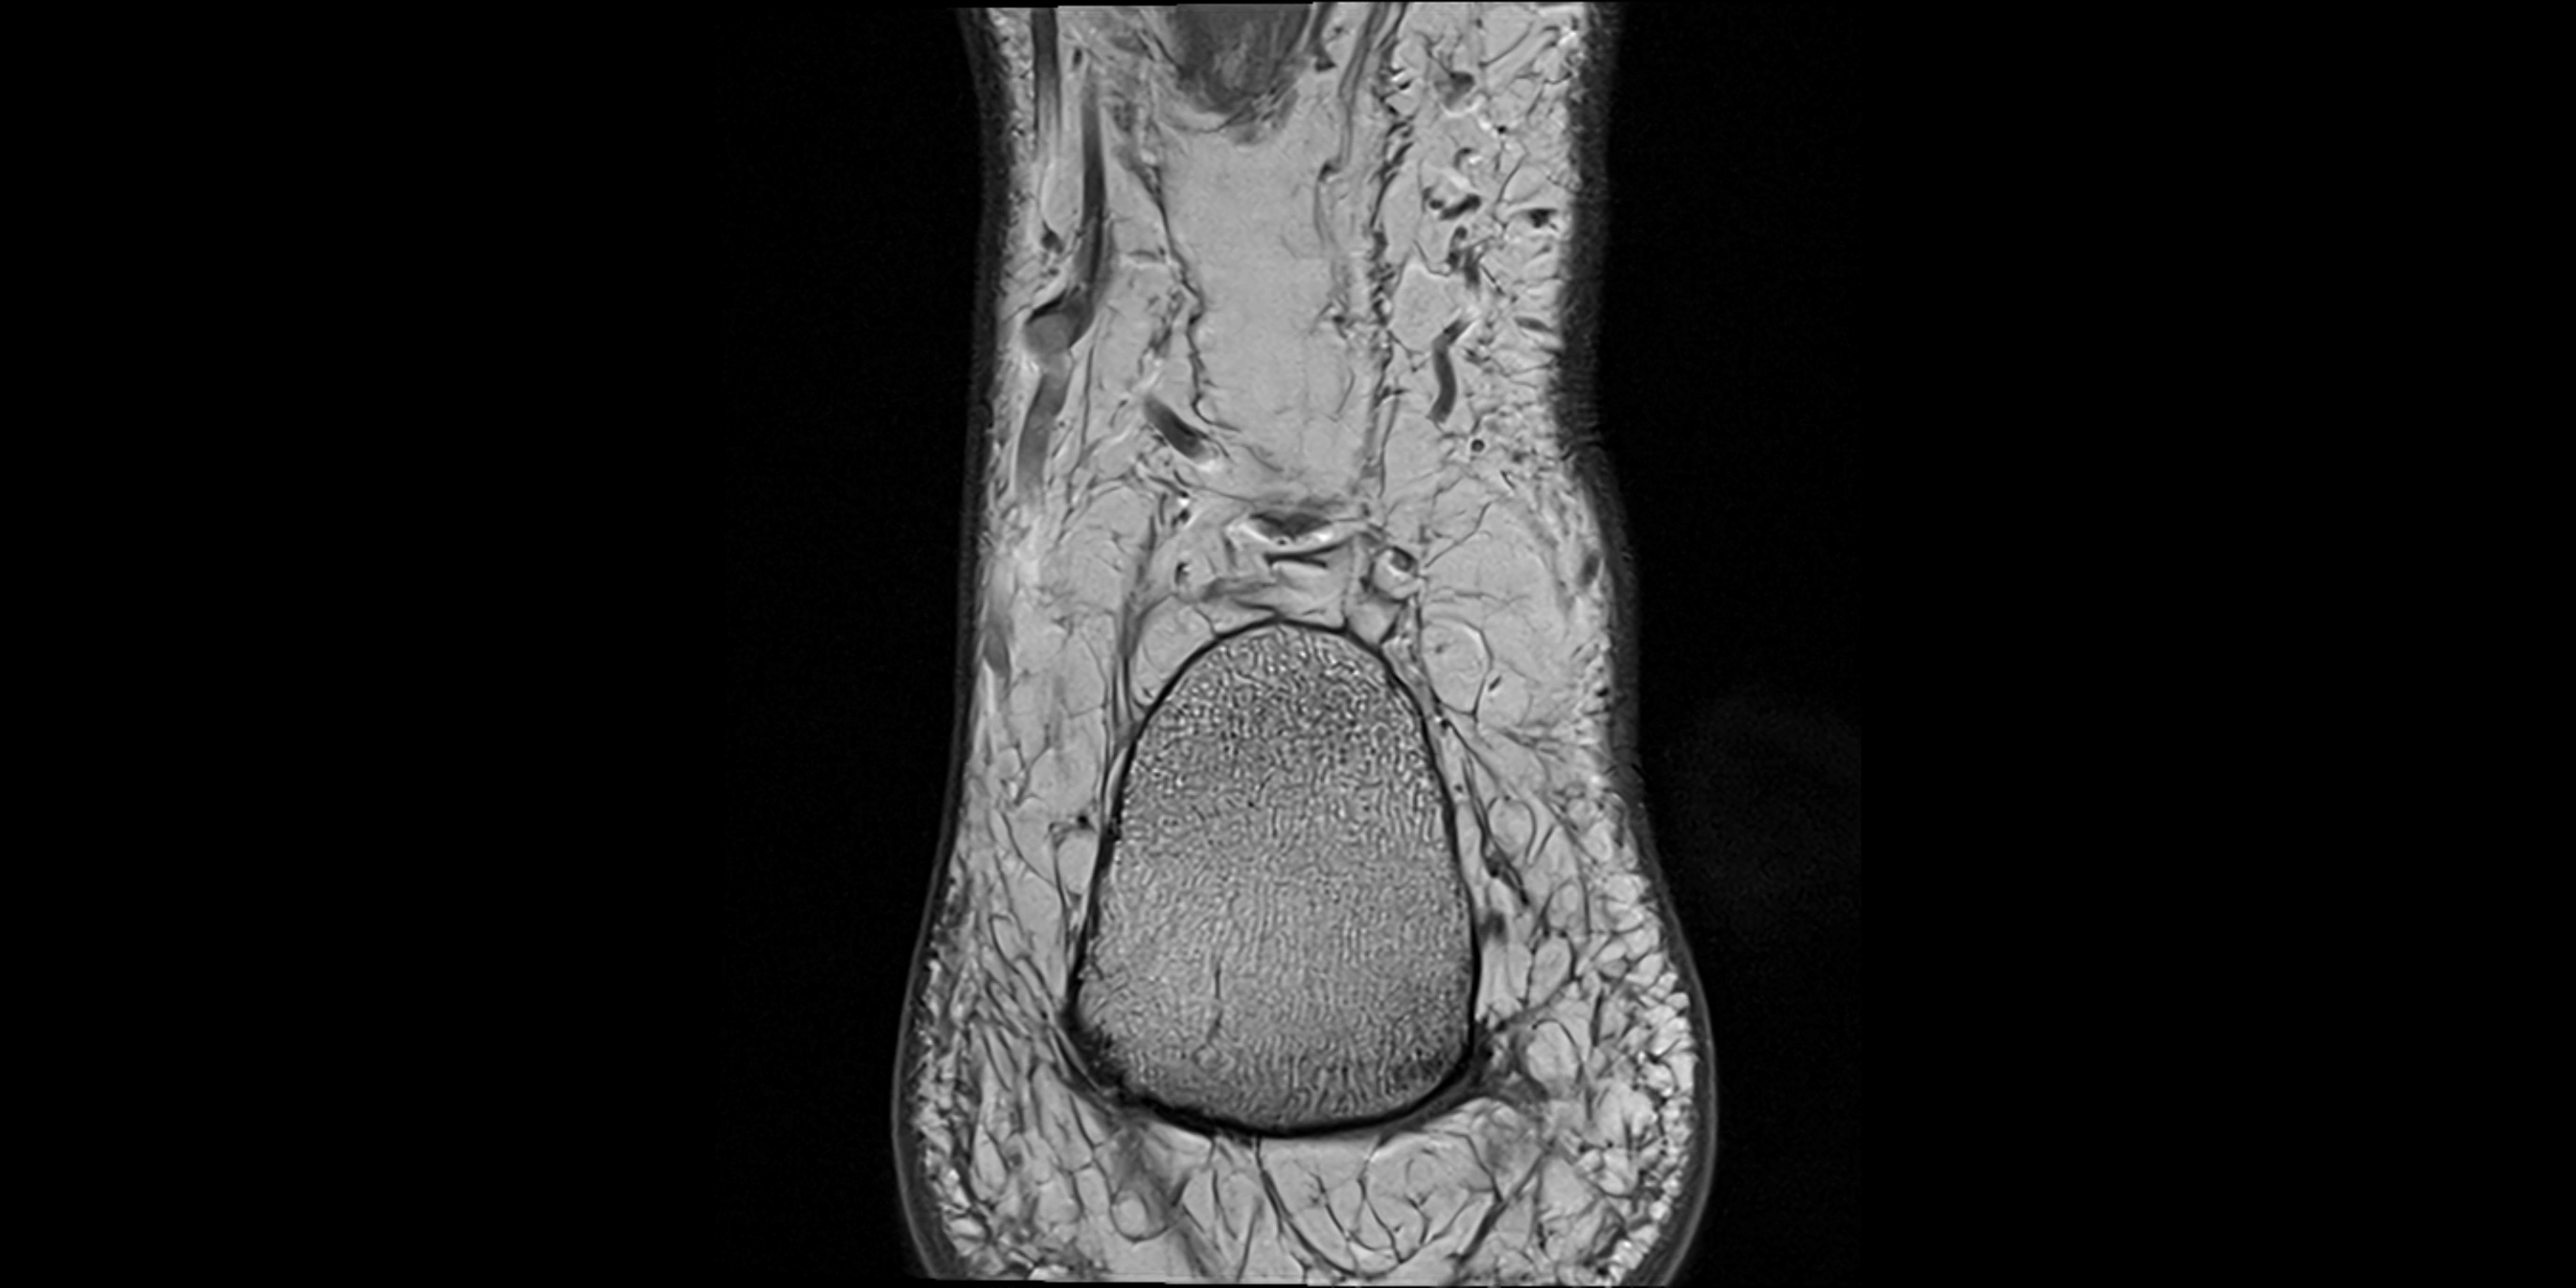

MRI image

image

MRI Appearance

• T1-weighted images:

• Muscle belly: intermediate signal intensity with visible fascicular structure

• Tendon: low signal (dark linear band) extending to the base of the fifth toe

• Surrounding fat: bright, outlining tendon and muscle course

• Partial tear or tendinopathy: focal thickening with increased intermediate signal intensity

• T2-weighted images:

• Normal muscle: intermediate-to-low signal, slightly darker than on T1

• Normal tendon: very low signal (dark), smooth and continuous

• Pathology: bright hyperintense foci along the tendon or myotendinous junction representing inflammation, edema, or partial tear

• Peritendinous fluid or sheath thickening appears as bright hyperintensity